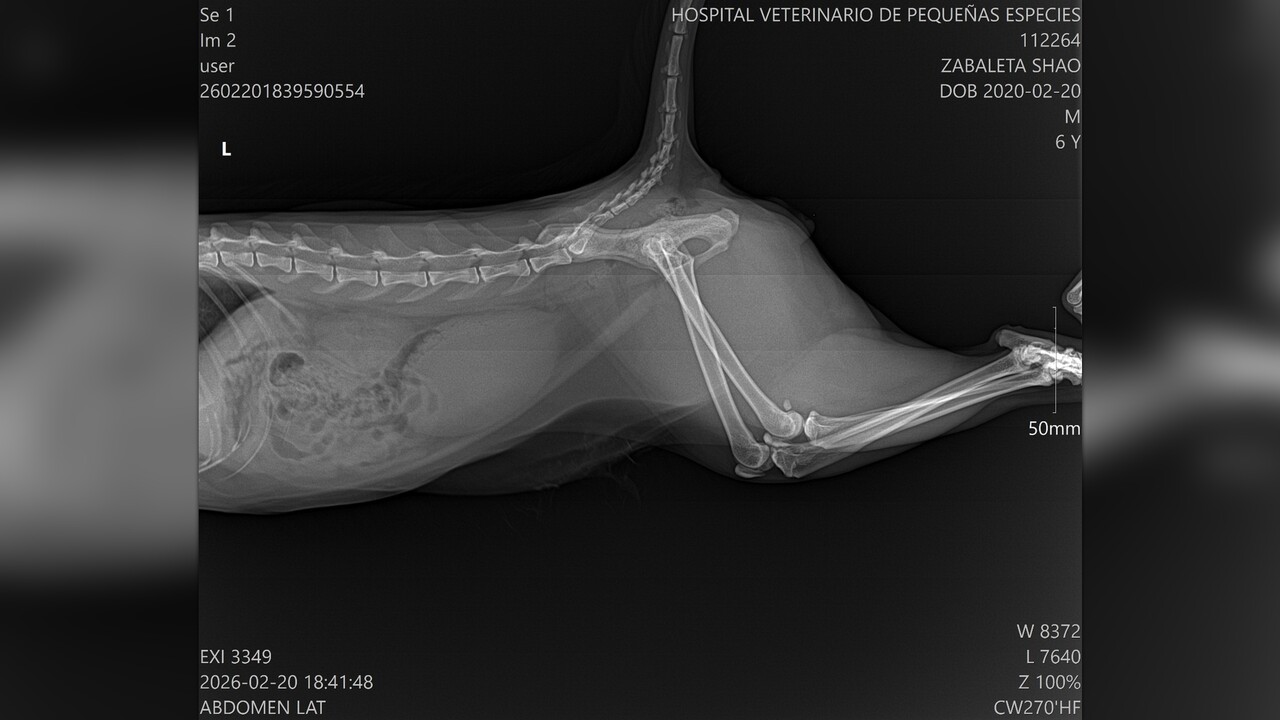

My orange cat is part of our family. We love him deeply and care for him like a child.

For more than two years, he has been suffering from chronic FLUTD and recurrent urinary blockages. During this time, I have spent over $2,000 USD on emergency visits, catheterizations, medications, and special care to keep him alive.

Recently, his condition has become more difficult to manage. His veterinarian has recommended that he stay strictly on Royal Canin SO urinary food for at least three months to prevent further blockages. Unfortunately, I am no longer financially able to afford both emergency care and his prescription food.

Without this diet, he is at high risk of another life-threatening obstruction. I am asking for help to purchase at least one large bag of SO urinary food so he can stabilize and recover properly.